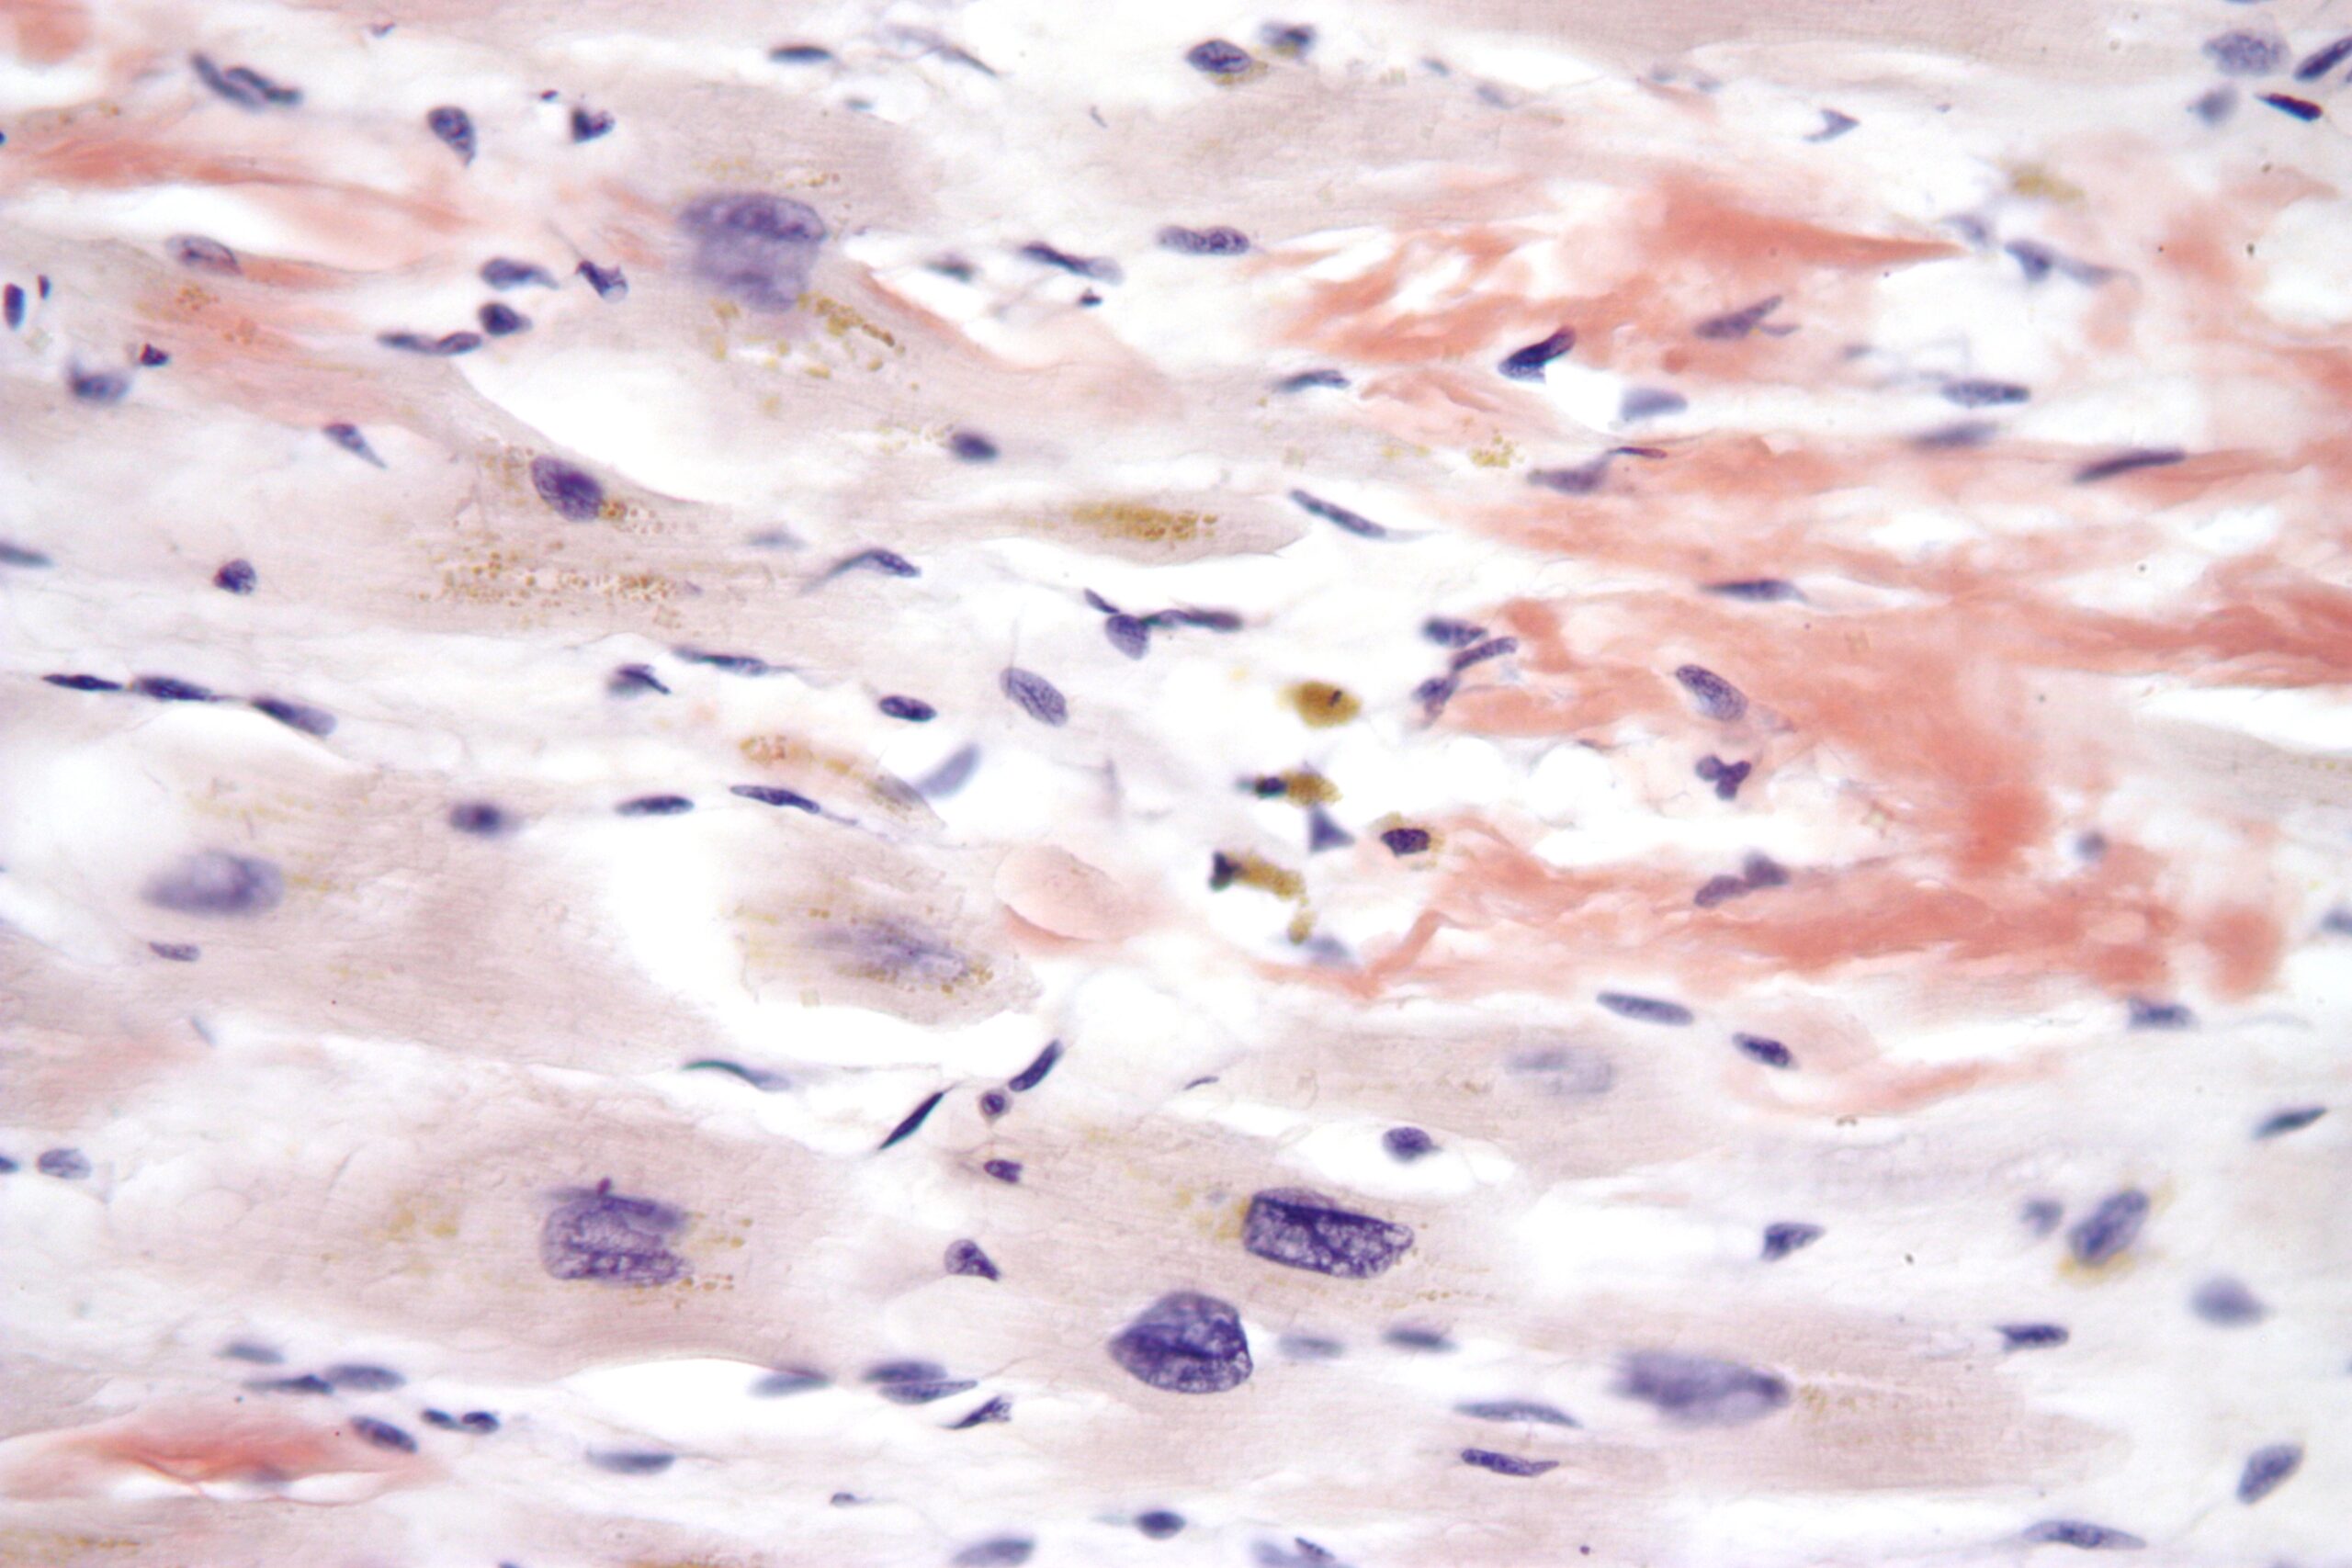

Micrograph of age-related cardiac amyloid. Licensed under the Creative Commons license (Wikimedia).